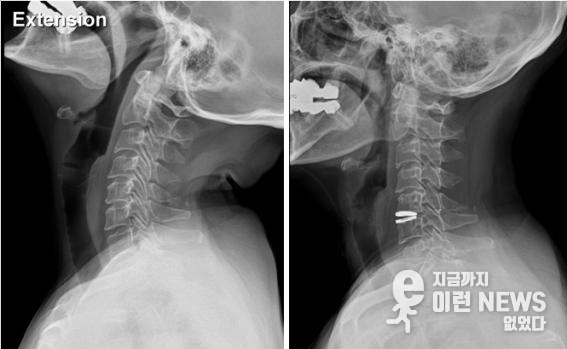

이러한 비수술 치료방법으로도 효과가 없다면 인공디스크와 같은 수술적 치료를 통해 치료를 고려해야 한다.